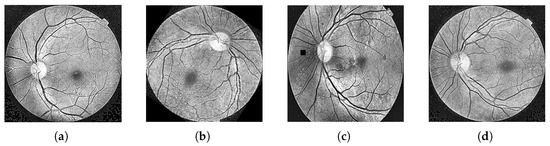

Diabetes is a chronic disease characterized by insufficient insulin secretion from the pancreas or a decrease in the body’s sensitivity to insulin, resulting in an increase in blood sugar levels [1,2,3]. According to the statistics of the China Diabetes Market Report: 2024–2032, China is presently the nation with the greatest number of diabetics globally, and the prevalence of diabetes has risen to about 12%. Long-term complications of diabetes can result in serious vision problems, with DR serving as the primary cause of blindness among individuals aged 20–64 [4]. DR is a severe eye complication resulting from diabetes, characterized by thinning of the retinal blood vessel wall, hemorrhage, fluid exudation, macular edema, and abnormal angiogenesis. These pathological changes may eventually lead to vision loss or even blindness [5]. The pathologic features of DR include microaneurysms (MAs), hard exudates (EXs), soft exudates (SEs), and hemorrhages (HEs) [6]. Based on the International Clinical Diabetic Retinopathy Scale (ICDRS), the types of DR are classified as normal, mild nonproliferative, moderately nonproliferative, severe nonproliferative, and proliferative. These five types of DR are illustrated in Figure 1 below.

Figure 1.

There are five types of DR: (a) DR0. (b) DR1, microaneurysm: a common phenomenon of early lesion DR, which is manifested as a dark red dot in the figure. (c) DR2, hemorrhage: the image is mostly a red lesion. (d) DR3, hard exudate: most of the bright yellow spots in the image are formed by lipid deposits caused by vascular leakage. (e) DR4, soft exudate: most of the spots in the picture are yellow/white spots.